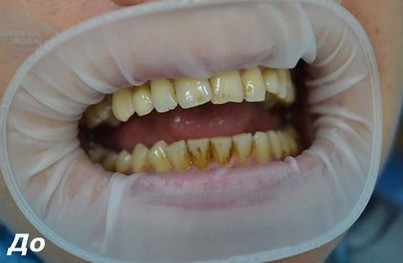

Чистка зубов Air-flow